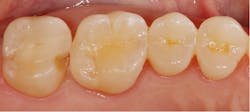

The data indicated that acid etched and adhesively bonded monolithic IPS e.max pressed lithium disilicate complete (97%) and partial (95%) coverage restorations exhibited excellent survival in the posterior teeth.

Ceramic materials have evolved dramatically over the last two decades,11 with so many ceramic materials that choice is based on personal preference and opinion, rather than evidence. One such widely spread opinion-based assumption is to avoid the use of lithium disilicate in posterior dentition due to high occlusal loads that could lead to premature fractures. In 2,392 posterior restorations studied over 17 years, only 22 fractures were recorded. Most failures occurred within the first 6 years and then declined, with five additional failures at 8 years. There were no additional failures in the 236 restorations with time in service of from 8 to 17 years. This declining failure rate suggests a lack of fatigue degradation in these longer-term restorations and will be explored in a future publication.

Of the 22 failures, 18 occurred in the molar region, and no debonding was seen. Our group has previously reported that Dicor glass ceramic has a higher risk of fracture in the molar region. Although there is also a trend of higher failure in the molar region for the lithium disilicate, no statistical significance was yielded. Even for the mandibular second molars that showed the highest failure rate (six failures), the estimated annual risk of failure was only 0.4% and without statistical significance. This provides evidence for choosing lithium disilicate for the molar region.

In the current study, the variable of thickness had no effect on the survival of complete and partial coverage restorations in the posterior teeth. The restorations with at least one surface with a thickness less than 1 mm performed similarly to those with a thickness of 1 mm or more. Similar findings have also been reported in clinical and in vitro studies.

These findings should encourage clinicians to be less invasive during preparation and minimize the clearance required for e.max lithium disilicate glass ceramic restorations to save as much of the tooth structure as possible.